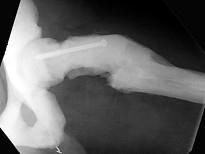

男,37岁,出现多处骨折,结合图像,最可能的诊断是?(?)A.石骨症B.成骨不全C.畸形性骨炎D.转移性骨肿瘤E.氟骨症

问题 男,37岁,出现多处骨折,结合图像,最可能的诊断是?(?)

选项 A.石骨症 B.成骨不全 C.畸形性骨炎 D.转移性骨肿瘤 E.氟骨症

答案 A